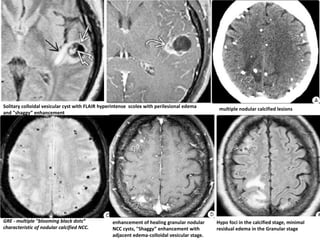

multiple nodular calcified lesions

Hypo foci in the calcified stage, minimal

GRE - multiple "blooming black dots“

characteristic of nodular calcified NCC.

enhancement of healing granular nodular

NCC cysts, "Shaggy” enhancement with

Solitary colloidal vesicular cyst with FLAIR hyperintense scolex with perilesional edema

and "shaggy” enhancement